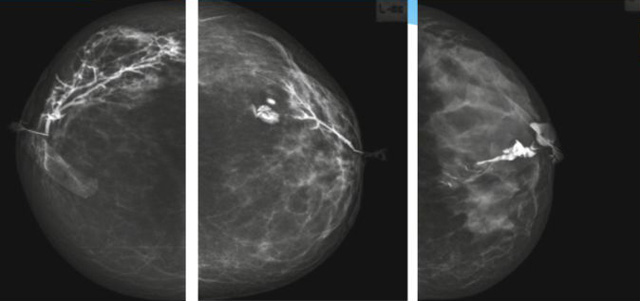

乳腺導管內(nèi)乳頭狀瘤乳腺超聲設備檢查的價值在哪里呢?

乳腺導管內(nèi)乳頭狀瘤分為以下兩個,位于乳暈區(qū)大導管的中央型乳頭狀瘤,起源于末梢導管小葉單位的外周型乳頭狀瘤。外周型乳頭狀瘤常常沒有明顯的的臨床表現(xiàn),常因X線或乳腺超聲設備檢查發(fā)現(xiàn)。重點要關注的是中央型乳頭狀瘤,發(fā)生于任何年齡的女性,以40~50歲者居多。它表現(xiàn)為:單側乳頭溢液,特別是血性溢液少數(shù)病人可在乳暈區(qū)觸及腫塊。從病理學上面講表現(xiàn)為導管上皮和間質(zhì)增生形成有纖維脈管束的乳頭狀結構。這是它一個病理學上的表現(xiàn)。它的超聲表現(xiàn)為:病變導管囊狀擴張呈無回聲,內(nèi)可見乳頭狀低回聲或中等回聲。乳暈處的導管擴張,管腔內(nèi)可見邊界清楚的,低回聲實性結節(jié)。外周型導管內(nèi)乳頭狀瘤可,表現(xiàn)擴張為為低回聲的實性結節(jié),CDFI:部分腫瘤可顯示為軸心性的看到血流信號。乳腺增生癥:可見導管擴張,內(nèi)無乳頭狀實性回聲,導管內(nèi)乳頭狀癌:囊內(nèi)乳頭狀癌病變較大,不規(guī)則,厚基底,血流豐富。以囊性為主的混合回聲,形態(tài)不規(guī)則,內(nèi)見實性低回聲實性低回聲可見少量血流,病理為囊內(nèi)乳頭狀癌。

乳腺超聲設備檢查的價值在哪里呢?它可以檢查發(fā)現(xiàn)乳暈周圍的各種病變,對于單側乳頭溢液、血性溢液的患者,超聲是首選的影像學檢查方法。注意:導管內(nèi)乳頭狀瘤可合并不典型增生或,導管內(nèi)乳頭狀癌,手術前懷疑時候,就應該手術切除而不是用微創(chuàng)手術。